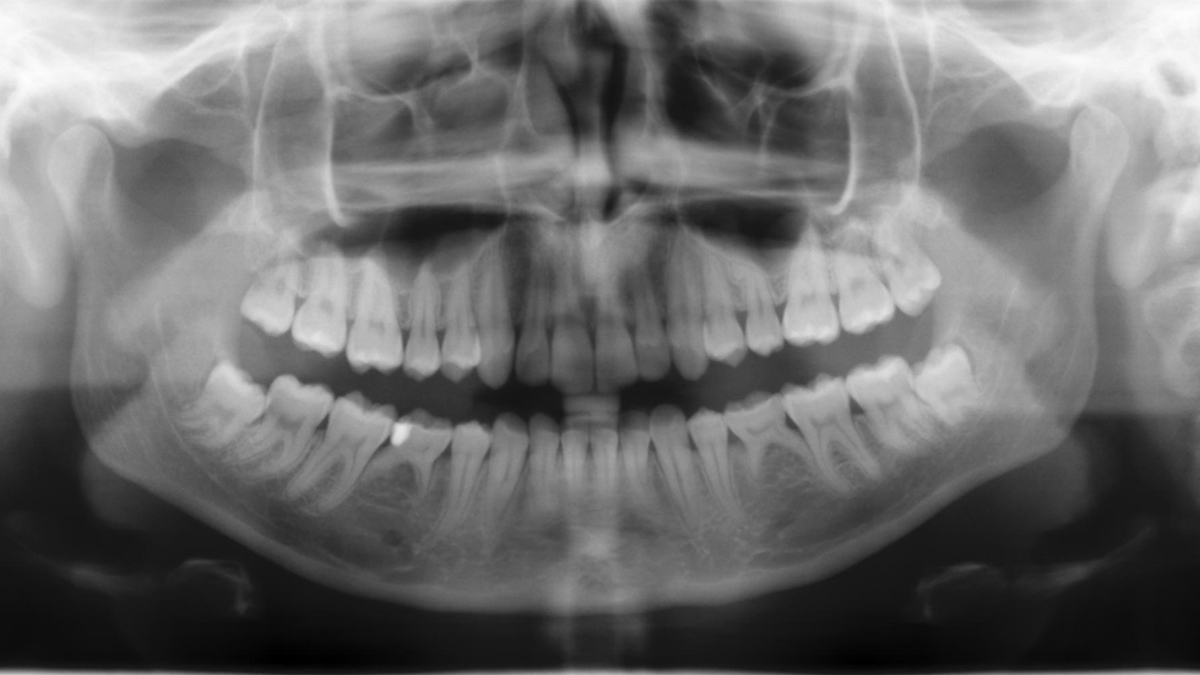

Panoramic image quality is constantly evolving

To the left: 10-year-old PAN image. To the right: DCS image taken with Orthophos SL